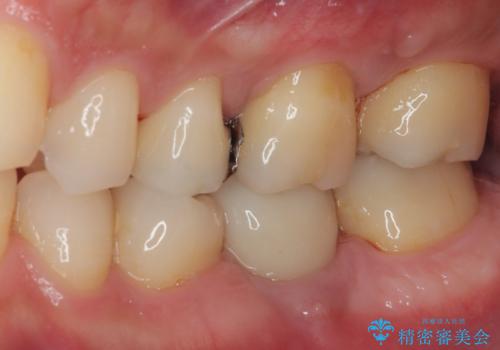

歯肉が腫れてズキズキする 奥歯の根管治療